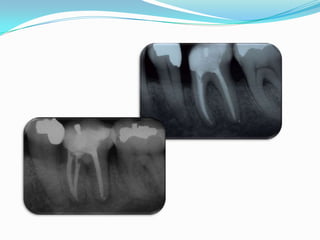

Caso Clínico

o   Nombre: Raquel Valenciano

o   Edad: 45 años

o   Ocupación: Secretaria

o   Motivo de Consulta: Dolor

o   Antecedentes Estado General: SDCP

o   Principio, Evolución y Estado Actual:

Hace 1 año dolor espontaneo de larga

duración. Evolucionó asintomático.

Actualmente dolor a la masticación         Inspección: Restauración de

o   Pieza Dental Problema: 36                  amalgama recidiva

o   Interpretación Radiográfica:               Sensibilidad al Frio: Negativo

Palpación: Positiva

Anatomía pulpar: espacio pulpar

Percusión: Positivo

reducido. IRL periapical en raíz distal.

LP ensanchado en raíz mesial.                  Diagnóstico Tentativo:

IRO compatible con material obturador         Periodontitis Apical Crónica

•   Tratamiento: Conductoterapia                          Agudizada

Caso Clínico o Nombre: Raquel Valenciano o Edad: 45 años o Ocupación: Secretaria o Motivo de Consulta: Dolor o Antecedentes Estado General: SDCP o Principio, Evolución y Estado Actual: Hace 1 año dolor espontaneo de larga duración. Evolucionó asintomático. Actualmente dolor a la masticación Inspección: Restauración de o Pieza Dental Problema: 36 amalgama recidiva o Interpretación Radiográfica: Sensibilidad al Frio: Negativo Palpación: Positiva Anatomía pulpar: espacio pulpar Percusión: Positivo reducido. IRL periapical en raíz distal. LP ensanchado en raíz mesial. Diagnóstico Tentativo: IRO compatible con material obturador Periodontitis Apical Crónica • Tratamiento: Conductoterapia Agudizada